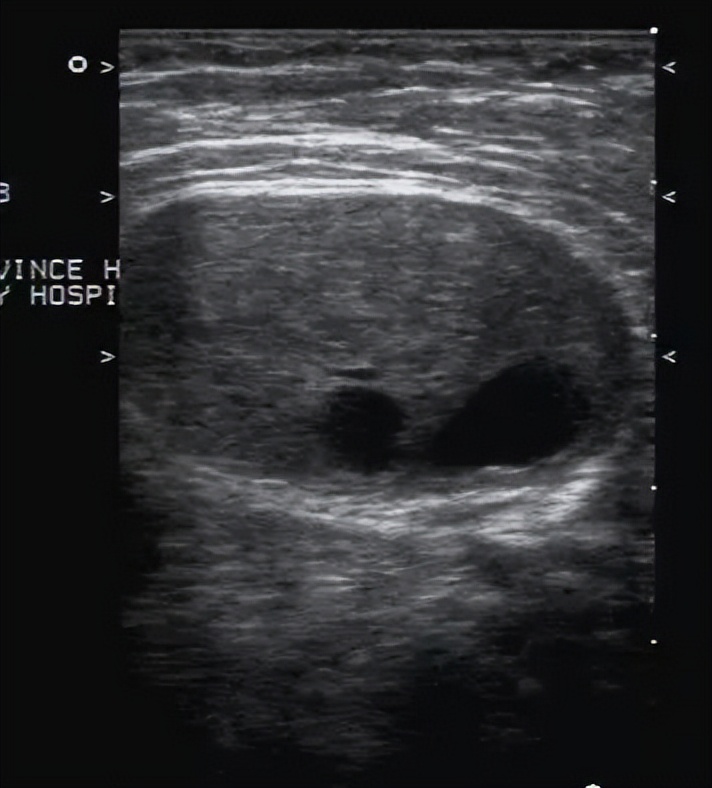

8. 腋下淋巴管囊肿:表现为囊性包块,内可有分隔